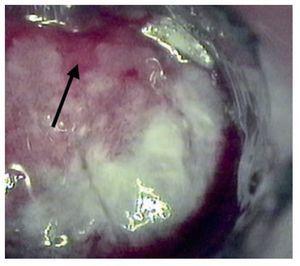

La anoscopia de alta resolución se realizó mediante la siguiente técnica: previa firma del consentimiento informado y con paciente en posición proctológica, se realizó tacto rectal para dilatación del ano, se introdujo anoscopio y se revisó el conducto anal en búsqueda de lesiones macroscópicas. Se aplicó ácido acético a 3% con un hisopo y se retiró el anoscopio. El hisopo se dejó en contacto con las paredes el conducto anal por un minuto y se retiró. Se introdujo nuevamente el anoscopio y se realizó la observación del conducto anal con microscopio de alta resolución. En los casos que se consideró necesario, a criterio del colposcopista, se utilizó la prueba de Schiling para detectar las lesiones sospechosas. Esta prueba consiste en aplicar una solución yodoyodurada de lugol a 1% o 2%, con el objeto de obtener imágenes yodo negativas (que no fijan el lugol), yodo positivas o yodo débiles (que fijan el lugol). El fundamento es que únicamente los tejidos maduros, provistos de glucógeno fijan el yodo, razón por la que el epitelio maligno o atípico es yodo negativo (Figuras 1-3). En las lesiones que resultaron dudosas para VPH o NIA se tomaron 1 o 2 biopsias de la lesión sospechosa. Previo al procedimiento, los pacientes acudieron con preparación intestinal a base de enemas de fosfato. No se administró profilaxis antibiótica y el procedimiento se realizó sin anestesia.

Figura 1. Anoscopia de alta resolución que muestra un patrón acetoblanca difuso. Se observa la línea de transición anorrectal. Por arriba de ella se observa el epitelio columnar y por debajo, el epitelio escamoso